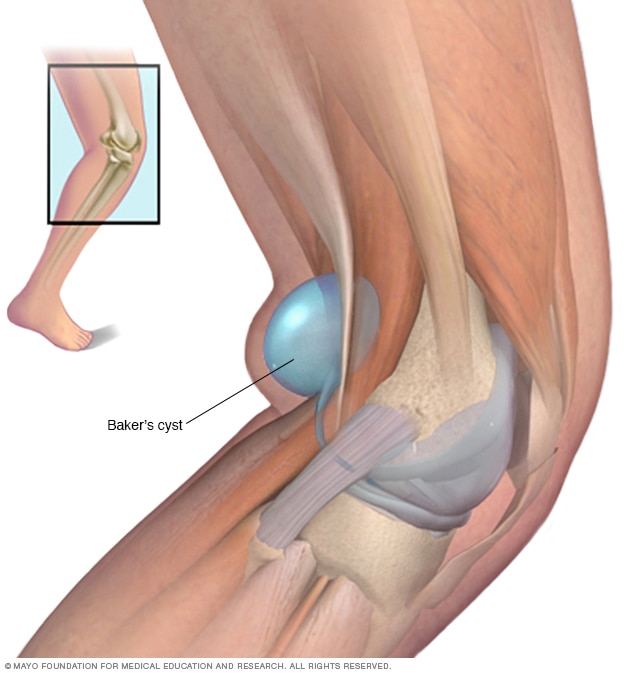

Torbiel Bakera, niekiedy również nazywana cystą Bakera, umiejscowiona jest pod kolanem. Mimo że uważana jest za chorobę niegroźną, może uszkadzić sploty naczyń krwionośnych oraz nerwy. Jest ona łatwo wykrywalna podczas badania palpacyjnego czyli krótko mówiąc poprzez dotyk.

Torbiel Bakera jest wypełniona płynem i zlokalizowana za kolanem. Nazwa pochodzi od lekarza (chirurga) Williama Baker’a, który po raz pierwszy opisał tą dolegliwość w 1877 r. Niekiedy używa się też nazwy torbiel podkolanowa lub torbiel dołu podkolanowego. Torbiele mogą różnić się wielkością, od bardzo małej do dużej, która mierzy wiele centymetrów. Rzadko cysta Bakera rozwija się na obu kolanach jednocześnie.

Jednak główną przyczyną powstania cysty Bakera jest nadmiar płynu stawowego lub uszkodzenie torebki stawowej. Staw kolanowy ma 2 powierzchnie pokryte chrząstką stawową i połączone ze sobą w sposób ruchomy. Rolą chrząstki stawowej, która pokrywa powierzchnie stawowe, jest zmniejszenie tarcia pomiędzy nimi.

Staw otoczony jest torebką maziową, która wypełniona jest płynem stawowym. Płyn ten odpowiedzialny jest za nawilżanie chrząstek oraz redukcję tarcia pomiędzy kośćmi w stawie podczas chodzenia. Ze względu na rolę płynu stawowego i ograniczoną objętość torebki maziowej zarówno zbyt mała, jak i zbyt duża ilość płynu stawowego jest niepożądana. Jeśli występuje w nadmiarze, może przeciekać przez uszkodzoną torebkę stawową czy też prowadzić do powstania torbieli.